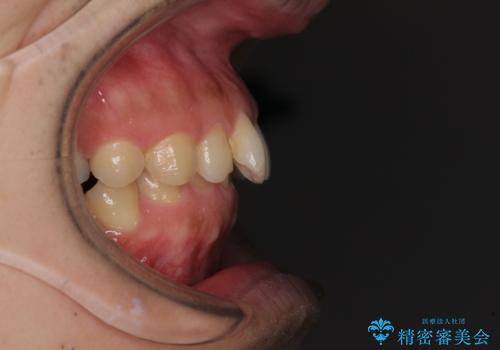

下顎前歯が見えなくなるくらいに深い咬み合わせであり、さらに上顎の正中が開くほど下の前歯が突き上げている状態でした。

奥歯は手前に倒れてしまっているため、後方に起き上がらせることで深い咬み合わせ・ディープバイトを改善する必要があります。

右上と左下は永久歯が欠如しており、大きさの大きく異なる乳歯が残存していたため、奥歯の咬み合わせを構築するために苦労しました。